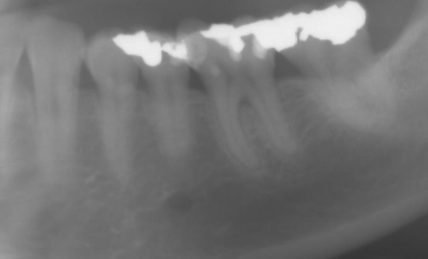

Ik voeg hierbij fotootje van het kwadrant linksonder vd OPK.

Wat is jullie opinie over de voorlaatste tand: ik zie daar ineens een donker vlekje .... kan dat een glitch zijn of zijn jullie eerder zeker overtuigd van een furcatie?

Het is inderdaad de 36 die ik bedoel (ik heb geen wijsheidstanden). Ik vind het tandbot daar precies erg laag? en zie dat donkere vlekje.